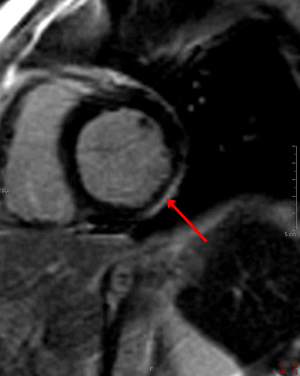

1) This gradient echo cine shows which of the following abnormalities?